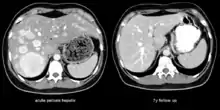

The CT scan of a patient with peliosis hepatis (left): The follow-up CT (right) after 7 years shows full remission.